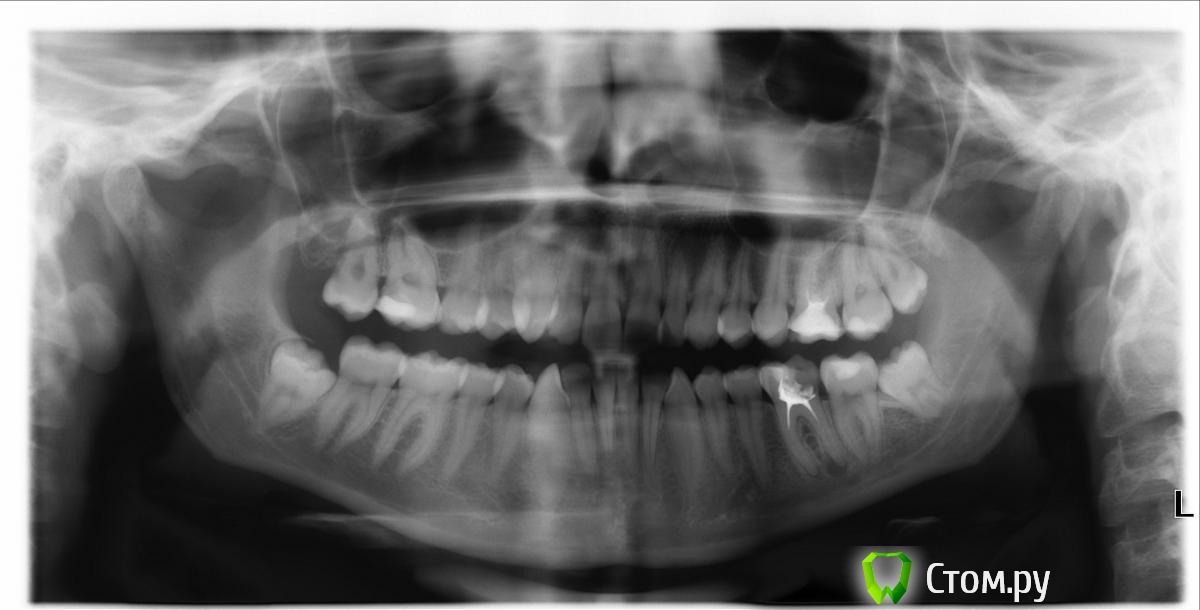

Александр Че74 Опубликовано 5 мая, 2014 Поделиться Опубликовано 5 мая, 2014 Действия:1. анестезия2. убрал медиальную часть3. сепарация4. не вывихивается, коронка раскололась, видны апексы.5. при вывихивании дистального корня (как оказалось сросшийся с язычной стенкой ) он ушел в мягкие ткани, 30 минут поиска..достали)6.удалили медиальный. У КОГО - НИБУДЬ УХОДИЛИ ФРАГМЕНТЫ В МЯГКИЕ ТКАНИ? ПОДЕЛИТЕСЬ ОПЫТОМ. (т.к. у меня первый раз такой случай) Ссылка на комментарий

BORA Опубликовано 5 мая, 2014 Поделиться Опубликовано 5 мая, 2014 http://s006.radikal.ru/i215/1405/e7/bc97f5f48679.jpg треугольником распилить и выходит дистальный,потом медиальный Ссылка на комментарий

АнтонТЛТ Опубликовано 7 мая, 2014 Поделиться Опубликовано 7 мая, 2014 http://sc.uploads.ru/0hdgA.jpg 3 Ссылка на комментарий

АнтонТЛТ Опубликовано 8 мая, 2014 Поделиться Опубликовано 8 мая, 2014 Надо было тонким фисурным бором пройтись между корнем и язычной стенкой Ссылка на комментарий